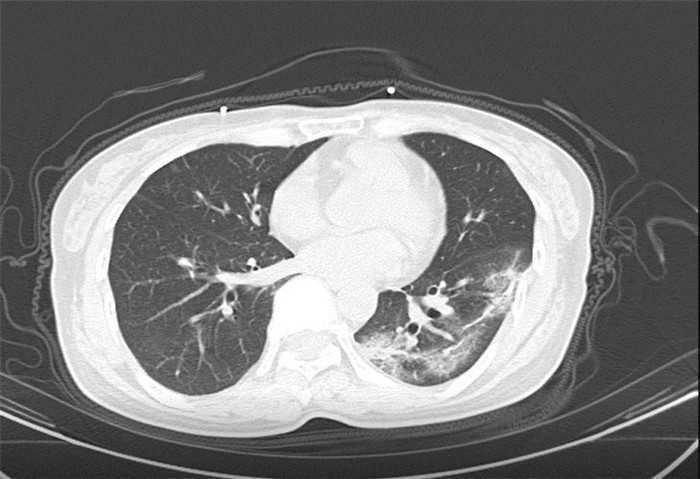

武漢大學(xué)中南醫(yī)院影像科副主任張笑春教授發(fā)現(xiàn),目前武漢市家庭聚集性發(fā)病較多,而且大多起病隱匿,一次甚至多次核酸陰性,無(wú)任何臨床癥狀,CT檢查卻已顯示為病毒性肺炎特征。

為了盡快篩查新型冠狀病毒肺炎患者,醫(yī)院會(huì)選擇影像診斷作為早期發(fā)現(xiàn)新型冠狀病毒感染的肺炎的重要一環(huán)。

CT為當(dāng)前首選篩查與診斷的主要影像學(xué)手段,胸部CT的病毒性肺炎檢出率高。

方舟CT(CT Ark)可以滿足全面的臨床功能,配置16層、32層、64層、128層CT,實(shí)現(xiàn)了低劑量掃描要求,配合NDI微劑量迭代技術(shù),智能毫安調(diào)控技術(shù),使各種場(chǎng)合下、各部位低劑量掃描得以實(shí)現(xiàn);超高分辨率CT病灶靶掃描,使病灶的密度顯示更加精確,能夠顯示病灶內(nèi)輕度的密度變化,有利于小病灶的密度定量分析和及時(shí)診斷。